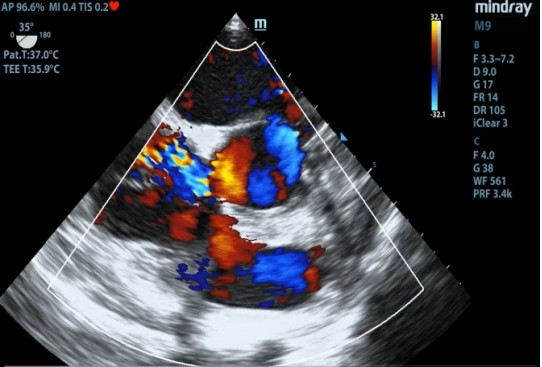

1 资料与方法患者女性,19岁,因“突发胸痛14 h”入院。患者14 h前无明显诱因出现胸骨后疼痛,呈紧缩感,伴有胸闷、呼吸困难,间断咳嗽。近期有听力下降、腹泻病史。8 h前就诊于外院时查体:体温测不出,Bp 53/36 mmHg(1 mmHg=0.133 kPa),呼吸40次/min, 脉搏137次/min,SPO2 93%,神志淡漠,全身皮肤湿冷,黏膜无黄染及出血点,颈静脉无怒张。听诊双肺呼吸音粗,可闻及满肺湿啰音,心音不清,腹部查体无异常,双下肢足背动脉搏动对称。化验结果提示WBC 29.3×109/L,NE 85.4%,TnT 93 ng/L,pro-BNP 2 047 pg/mL,PCT 0.11 ng/mL, 血气分析:pH 7.349,PCO2 31.2mmHg,PO2 67.2 mmHg,HCO3- 17.2 mmol/L,Lac 5.7 mmol/L。心电图提示:窦性心动过速、AVR导联ST段抬高,余导联ST段压低;床旁心脏超声提示EF 52%,二尖瓣中度返流、三尖瓣中重度返流,未见室壁节段性运动性异常。考虑心源性休克,原因尚不明确,给予机械通气、血管活性药物、补液等抗休克治疗,同时联系本院急诊ECMO团队,本院急诊ECMO团队到达现场后,患者突然出现室颤,给予胸外按压及电除颤后逐渐恢复窦律,立即进行V-A ECMO上机指征及预后评分SAVE评分评估,符合V-A ECMO上机适应证,约30 min成功上机运转,流量3.5 L/min,复查外周动脉血气分析: pH 7.305,PCO2 21 mmHg,PO2 73.4 mmHg,HCO3- 10.5 mmol/L,Lac 8.4 mmol/L。后转运至本院急诊病房,转运途中行生命体征、血气分析、ACT等常规监测,至病房后患者ECMO支持下血压仍需大剂量血管活性药物维持且脉压差较小,观察ECMO动静脉管路颜色极为接近,床旁经胸心脏超声提示主动脉瓣重度返流,为明确原因立即行急诊CT检查及床旁经食道超声心动图检查。本院肺CT(图 1)提示肺水肿,床旁经胸心脏超声提示主动脉瓣大量返流但心室收缩可,请超声影像科进一步行床旁经食道超声检查提示无冠窦呈瘤样凸向右房侧,瘤壁上可见宽约0.6 cm破口;主动脉瓣舒张期无冠瓣脱向左室流出道侧(图 2、图 3)。立即请心血管外科会诊,急诊行主动脉瓣机械瓣膜置换术+主动脉窦修补术+房间隔造口术+主动脉球囊反搏置入术+心脏起搏器置入术,术中探查与经食道超声所见相符(图 4、图 5),考虑左心功能差,左心压力较高,行房间隔造口术。术后复查胸片肺水肿基本消失(图 6),继续呼吸机与ECMO支持,因患者肺功能良好,自主呼吸良好,为减少呼吸机相关肺损伤、呼吸机相关肺炎等发生,术后第4天神志清醒后拔除气管插管,机械通气减轻左心前后负荷的作用去除后,继续ECMO与IABP支持,ECMO增加左心后负荷时IABP可降低左室后负荷,达到左心减压的目的,术后第10天心功能恢复,下调ECMO流量后循环可维持,予以撤离ECMO,术后第12天撤离IABP,后停用肝素持续泵入抗凝,达肝素皮下注射联用华法林口服抗凝3 d后,单用华法林口服抗凝,维持INR达标,在康复期间患者活动时左下肢疼痛,左侧足背动脉搏动减弱,下肢动静脉超声提示左侧股浅动脉血栓形成,期间增加华法林剂量后血栓未见明显变化,后行下肢股浅动脉切开取栓术,术后33 d患者完全康复顺利出院。

| 图 6 术后胸片 |

因患者生命体征难以维持并出现室颤,经初始评估符合V-A ECMO上机适应证,预后评分生存率较高,遂紧急行V-A ECMO,上机初期动静脉导管内颜色差别较明显,很快两导管内颜色难以区分,考虑原因为充分氧合的左心血通过破口直接进入右心房被引出,自身形成“再循环”使得动静脉导管颜色相近。根据2021年ELSO成人心脏病患者V-A ECMO指南,对ECMO功能有影响的病因如主动脉瓣关闭不全为V-A ECMO潜在禁忌证[9],理论上患者行V-A ECMO后主动脉与右心之间的压力差会进一步增大,左向右分流增加,心源性休克进行性加重且随时可能出现心脏停搏,但患者已出现室颤,病因未明确情况下经目前治疗仍随时会出现呼吸心搏骤停,且通过精确的ECMO流量滴定可减少右心容量负荷,同时相对减小主动脉与右心之间的压力差,为后续寻找病因及治疗争取时间。V-A ECMO也同样适用于心脏术后心功能尚未恢复的患者,本例患者因术后心功能较差未能立即撤机,继续V-A ECMO支持治疗,待心功能恢复后才撤机。V-A ECMO的适应证在临床上不断被拓宽,其精准使用可以为存在相对禁忌证的患者的后续诊治争取时间。但本例患者治疗期间也出现了V-A ECMO的常见并发症:左心压力增加及下肢动脉缺血。V-A ECMO辅助下因左心室后负荷增加引起左室扩张,易出现左房增大、肺水肿、血流瘀滞形成血栓等,不利于心肌的恢复,术中行房间隔造口术减轻左心压力;术后出现下肢动脉缺血,股浅动脉内出现血栓经抗凝治疗无效后行下肢动脉切开取栓术。